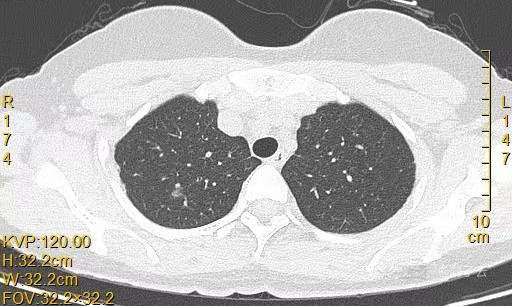

患者女,44岁,无特殊症状,做体检时发现右肺结节。查到1年前的体检CT片,右上肺当时就有一个直径约3mm的微小结节。两次检查检查图片如下:

以下三张为1年前CT片: